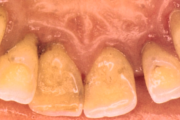

Krooniline parodontiit

Krooniline parodontiit on mikroobide poolt põhjustatud hammaste tugikudede põletik, mille tulemusena tekib progresseeruv alveolaarluu (nähtav röntgenograamil) ja periodontaalligamendi destruktsioon, igemetaskute moodustumine, igeme retsessioon või mõlemad kahjustused kombineeritult. Loe edasi »

- igemed punetavad (21)

- ige on paistes (mädapunn)

- igemed on tursunud/vohavad (17)

- puudulik suuhügieen (5)

- igemepealne hambakivi (5)

- halb hingeõhk / suu haiseb (12)

- halb maitse suus (12)